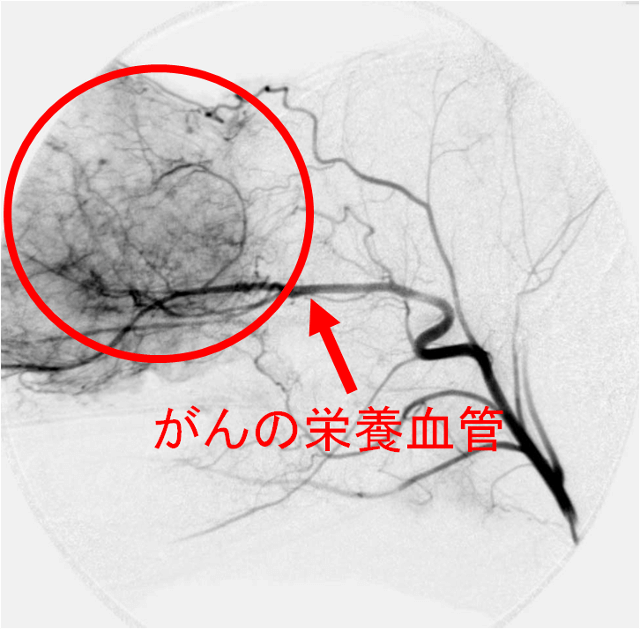

A:がんが増殖して大きくなるためには、血液からの栄養が必要です。

そのためにがんは、近くにもともとあった正常な血管(動脈)から枝分かれするような「がん栄養血管」という新しい血管を自ら作り、がんの中に血液を取り込みます(図1)。

(図1)